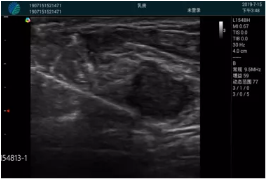

腺體內部清晰顯示一低回聲塊影,形態(tài)不規(guī)則,邊界模糊,邊緣呈毛刺狀,內部見砂礫樣鈣化

M20引導下穿刺活檢術

M20引導下平面內穿刺取出的腫塊組織